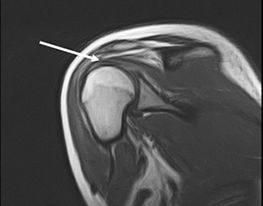

Ми провели МРТ обстеження, при якому виявлено пошкодження надостного м'яза (вказано стрілкою). Пацієнтці було виконано оперативне відновлення пошкодженого м'яза.